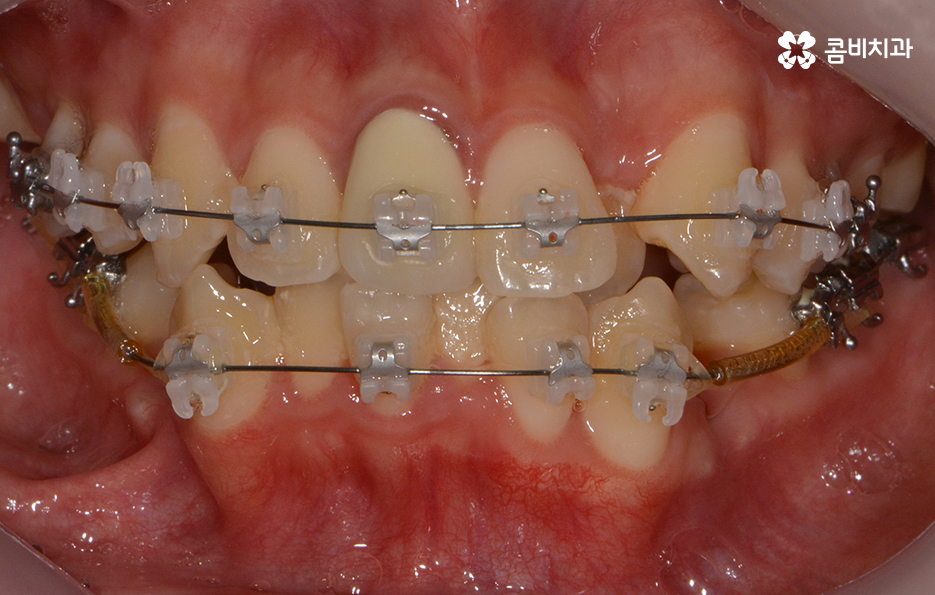

참고로 이번 포스팅에 소개해드린 환자분의 경우

검진부터 발치, 클리피씨 교정을 통해 교정이

마무리 되기 까지 약 2년 정도가 걸렸으며

치료 기간은 개인에 따라 상이하며 정확한 검진 후에

치료 계획에 따라 달라질 수 있어요.